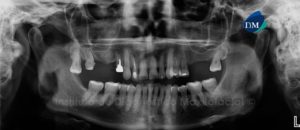

Paciente de sexo masculino de 45 años se acerca al Instituto de Diagnóstico Maxilofacial para evaluación integral por motivos de colocación de implantes. A la